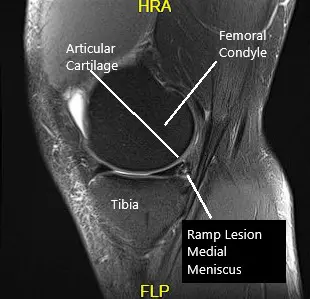

La resonancia magnética de la rodilla izquierda sugirió una compleja rotura del cuerno posterior del menisco medial. Pequeña ruptura horizontal del cuerpo del menisco lateral. Derrame articular moderado con sinovitis.

Resonancia magnética de la rodilla en la sección sagital y coronal.